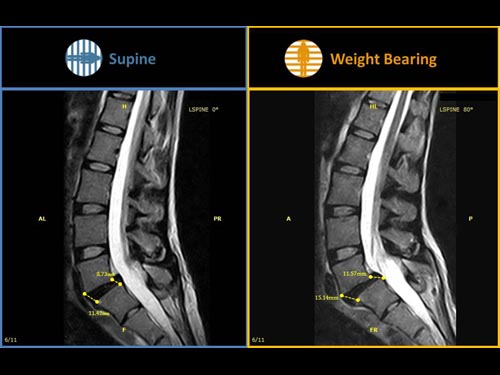

- Sistemos pavertimo funkcija leidžia atlikti MRT tyrimus esant realioms sąnarių ar stuburo diskų apkrovoms